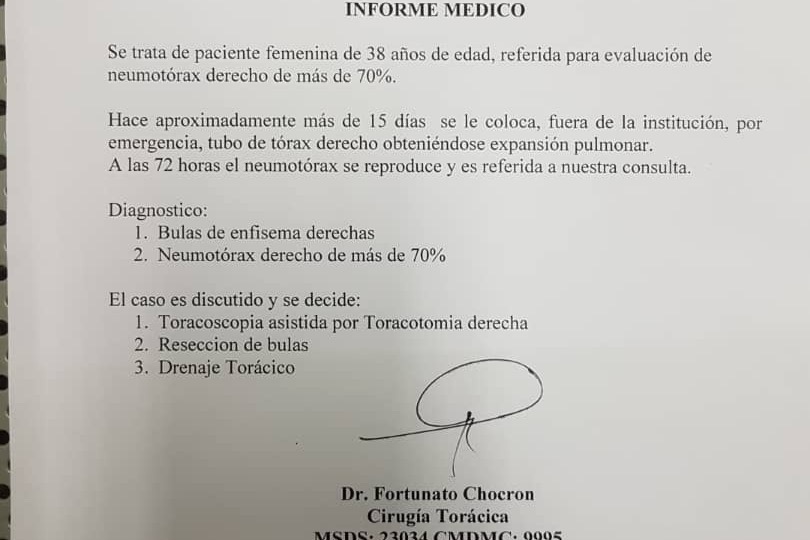

Dos semanas atrás nuestra querida Gaby tuvo dificultad para respirar. Jorgito la llevo a una clínica en Guarenas y fue diagnosticada con una "enfermedad bulosa pulmonar complicada con neumotorax derecho activo". Traduzco: una de las capas de tejido de su pulmón derecho tiene una condición donde se crea una burbuja de aire por dentro, comprimiendo el pulmón y limitando su expansion al momento de inhalar. En la clínica donde fue atendida, le hicieron un procedimiento sencillo que consta de insertar una suerte de manguera por el abdomen hasta el pulmón, y con ella extraer el vacío creado por la burbuja y lograr estabilizar su movimiento natural de expansion y retracción, con la finalidad de llevar su capacidad pulmonar de nuevo a un 100%. Este tratamiento duro 3 días y les costo poco mas de $2,000.

Lamentablemente, el día de ayer, luego de hacer examen post-operatorios para comprobar que no había reincidencia de la burbuja de aire, se percataron que su capacidad pulmonar había disminuido considerablemente de nuevo a menos de un 50%, por lo que la condición requeriría de una cirugía mas complicada y delicada. Esta nueva intervención consiste en abrir el tórax para tener acceso completo al pulmón, remover la capa de tejido que esta dañada, y proceder a cocer nuevamente el pulmón y su pecho. Tiene una duración de dos horas y posteriormente necesita estar hospitalizada tres días.

Luego de considerar las opciones disponibles, por recomendación del Dr. Fortunato Chocaron (quien procederá a operarla) decidieron hacer los tramites en la Clínica La Floresta, en Caracas. El costo de la operación suma un total de Bs. 18.136.550,00, lo cual al cambio representan $6,000.

Two weeks ago our beloved Gaby started having some breathing difficulties. Jorge took her to a clinic and she was later diagnosed with "pulmonary bullous disease complicated with active right pneumothorax". I'll explain: one of the outer tissue layers of her right lung developed a condition where it creates an inner air bubble, compressing the lung space and limiting its expansion when inhaling. She went under surgery at the hospital that day, where they basically put a sort of hose in her abdomen until her lung to be able to reduce the pressure of the bubble and extract the air trapped in it to restore lung capacity to 100%. This procedure took three days for completion and cost them $2,000.

Regrettably, yesterday, after the post-surgery tests meant to reassure that the issue was corrected and the lung activity restored, they found out her lung capacity went back down to under 50%, and a more complicated surgery is now needed. This time around, they need to open up her thorax to be able to fully access her lung, then they have to cut off the outer damaged layer and stitch back both her lung and her chest. This procedure lasts about two hours and she needs to be hospitalized for three days after.

After considering all options available, and by listening to Dr. Fortunato Chocaron's (who will perform the surgery) recommendation, they decided to do the procedure in Clinica La Floresta, Caracas. The overall cost is $6,000.

Dos semanas atrás nuestra querida Gaby tuvo dificultad para respirar. Jorgito la llevo a una clínica en Guarenas y fue diagnosticada con una "enfermedad bulosa pulmonar complicada con neumotorax derecho activo". Traduzco: una de las capas de tejido de su pulmón derecho tiene una condición donde se crea una burbuja de aire por dentro, comprimiendo el pulmón y limitando su expansion al momento de inhalar. En la clínica donde fue atendida, le hicieron un procedimiento sencillo que consta de insertar una suerte de manguera por el abdomen hasta el pulmón, y con ella extraer el vacío creado por la burbuja y lograr estabilizar su movimiento natural de expansion y retracción, con la finalidad de llevar su capacidad pulmonar de nuevo a un 100%. Este tratamiento duro 3 días y les costo poco mas de $2,000.

Lamentablemente, el día de ayer, luego de hacer examen post-operatorios para comprobar que no había reincidencia de la burbuja de aire, se percataron que su capacidad pulmonar había disminuido considerablemente de nuevo a menos de un 50%, por lo que la condición requeriría de una cirugía mas complicada y delicada. Esta nueva intervención consiste en abrir el tórax para tener acceso completo al pulmón, remover la capa de tejido que esta dañada, y proceder a cocer nuevamente el pulmón y su pecho. Tiene una duración de dos horas y posteriormente necesita estar hospitalizada tres días.

Luego de considerar las opciones disponibles, por recomendación del Dr. Fortunato Chocaron (quien procederá a operarla) decidieron hacer los tramites en la Clínica La Floresta, en Caracas. El costo de la operación suma un total de Bs. 18.136.550,00, lo cual al cambio representan $6,000.

Two weeks ago our beloved Gaby started having some breathing difficulties. Jorge took her to a clinic and she was later diagnosed with "pulmonary bullous disease complicated with active right pneumothorax". I'll explain: one of the outer tissue layers of her right lung developed a condition where it creates an inner air bubble, compressing the lung space and limiting its expansion when inhaling. She went under surgery at the hospital that day, where they basically put a sort of hose in her abdomen until her lung to be able to reduce the pressure of the bubble and extract the air trapped in it to restore lung capacity to 100%. This procedure took three days for completion and cost them $2,000.

Regrettably, yesterday, after the post-surgery tests meant to reassure that the issue was corrected and the lung activity restored, they found out her lung capacity went back down to under 50%, and a more complicated surgery is now needed. This time around, they need to open up her thorax to be able to fully access her lung, then they have to cut off the outer damaged layer and stitch back both her lung and her chest. This procedure lasts about two hours and she needs to be hospitalized for three days after.

After considering all options available, and by listening to Dr. Fortunato Chocaron's (who will perform the surgery) recommendation, they decided to do the procedure in Clinica La Floresta, Caracas. The overall cost is $6,000.